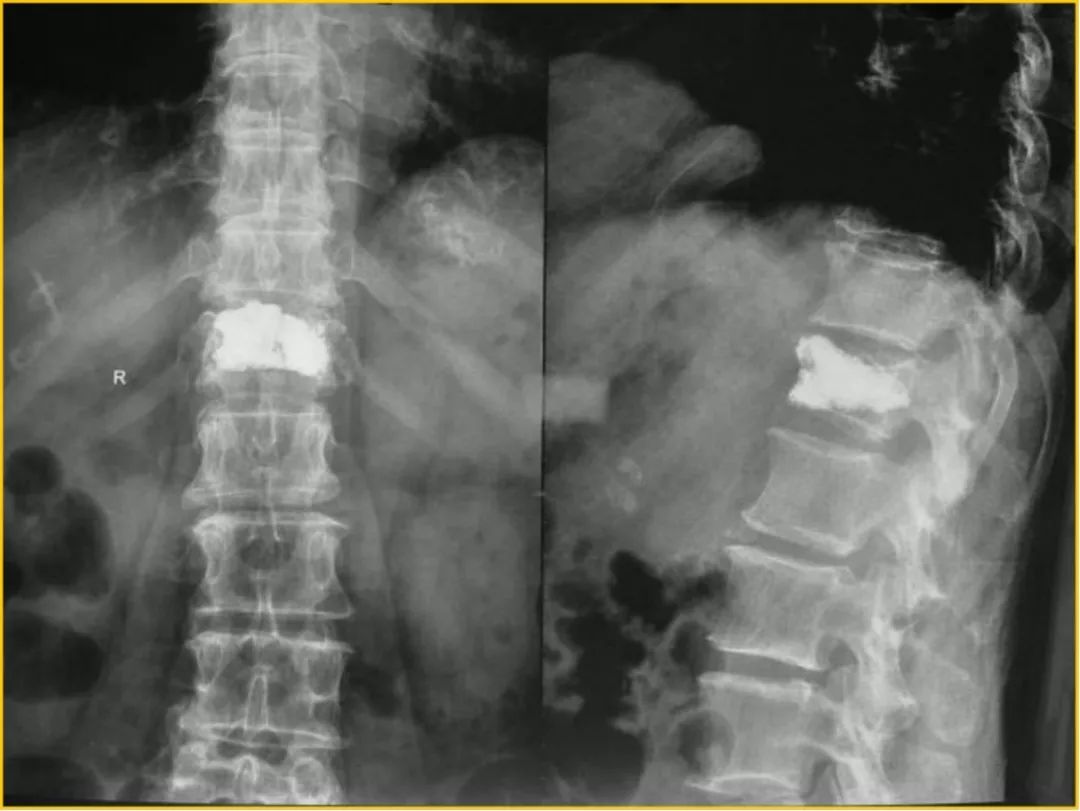

经过黄刚主任仔细地问诊和查体,初步诊断曹阿姨是椎体压缩骨折了,在完善胸腰椎的X线检查后,也证实了黄刚主任的推断。在与曹阿姨及家属充分沟通后,黄刚主任为曹阿姨行微创手术,术后疼痛马上缓解,隔天便可戴着护具下地,曹阿姨脸上也绽放出满意的笑容。

术前的椎体压缩骨折结果

手术后的正常椎体

压缩骨折一般疼痛比较剧烈,有负重体位如坐立,站立位和翻身时疼痛剧烈加重,静止卧床可减轻的特点,并可能连带下肢疼痛。如果椎体骨折严重,骨块可能会突入椎管压迫脊髓,导致肌肉瘫痪或感觉异常。另外由于身体前屈,椎体前部被压缩成楔形,从而导致驼背,摄X片多提示个别或部分椎体楔形变。